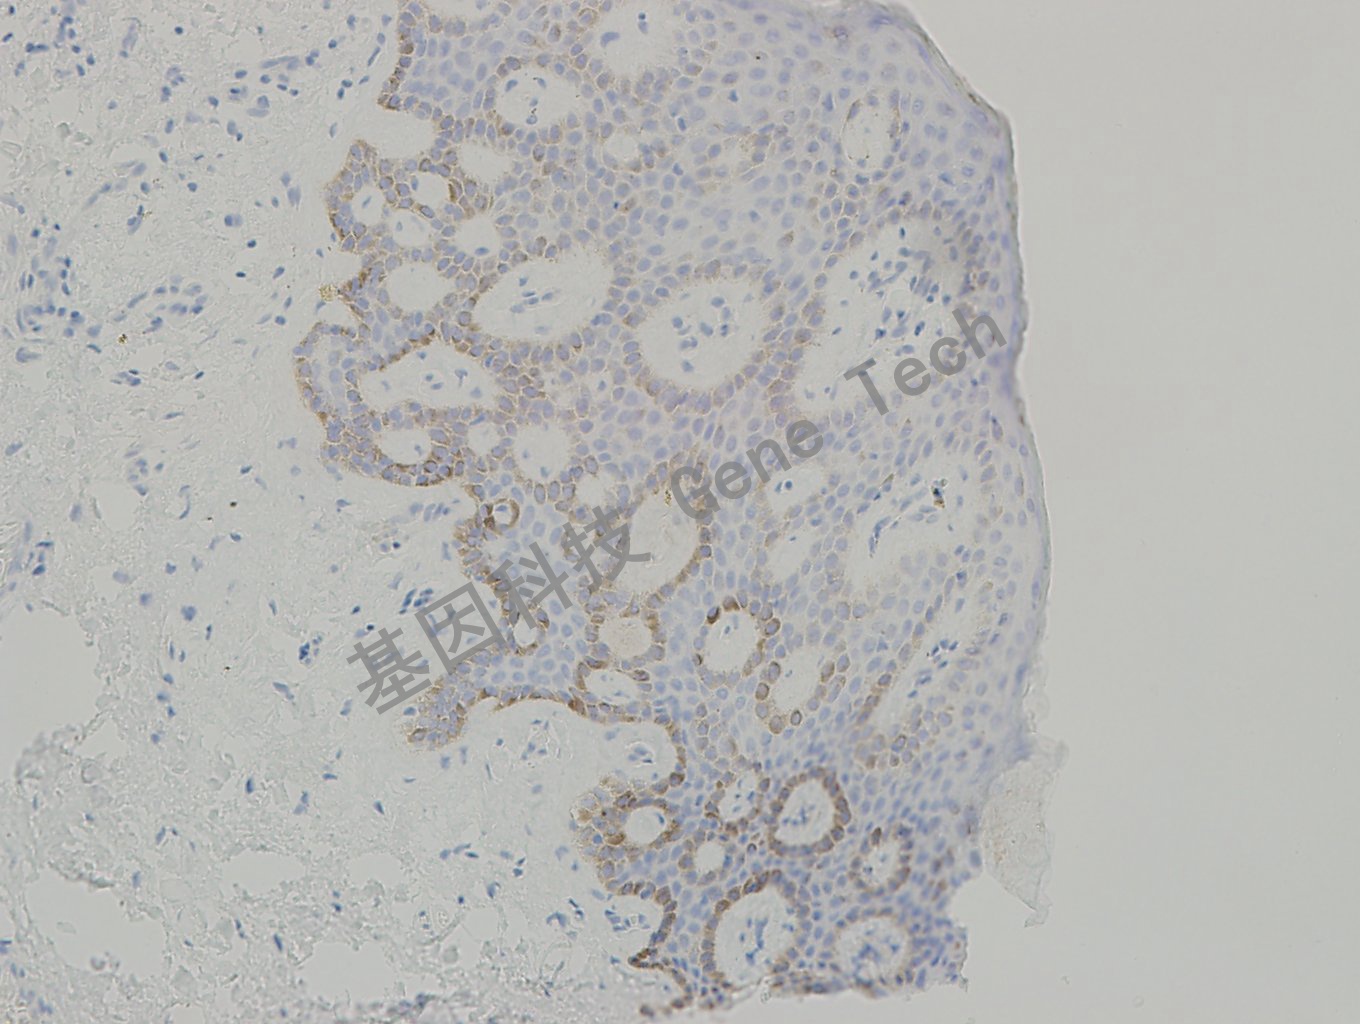

小叶原位癌石蜡切片,用 Collagen Type IV(GT2327)染色,基底膜阳性,DAB 显色。